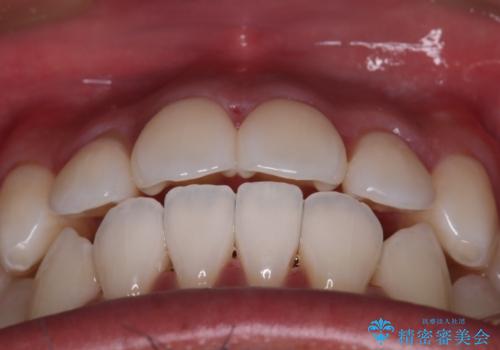

早く終わらせたいとの事でしたが、ゴム掛けを頑張っていただいたので

9ヶ月という短い期間で治療が完了しました。

矯正後は保定経過とメンテナンスで経過を見ていきます。